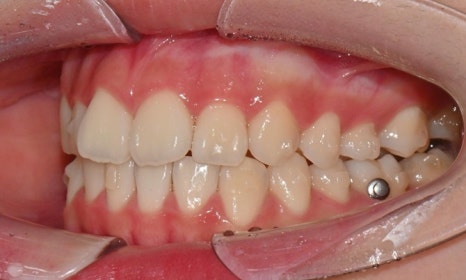

치료 시작 6개월 후 - 연세정원치과

치료 과정 중 환자는 장치 착용 시간을 매우 잘 지켜주었고, 내원 시마다 계획한 치아 이동이 비교적 정확하게 이루어지는 모습을 보였습니다. 이처럼 인비절라인 치료의 경우 환자의 협조도가 치료 결과에 큰 영향을 미치기 때문에, 이번 케이스에서는 환자의 성실한 장치 착용이 좋은 결과를 만드는 데 중요한 역할을 했다고 볼 수 있습니다.